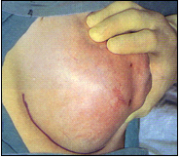

לעתים הכיסיות גדלות לממדים גדולים (תמונה 3.12), תוך ימים, בניגוד לקרצינומות הגדלות לאט. חלק מהכיסיות קטנות במשך הזמן ואף נעלמות.

במידה ולמרות הניקור המצב מחמיר אז יש לנקז את המורסה באופן כירורגי. בדרך כלל הגישה לניקוז המורסה היא על-ידי חתך מעליה, פתיחת המורסה, ניקוזה וניתוק כל הסרחות של רקמת החיבור שבתוך המורסה, וזאת על מנת לאפשר את ניקוזה המושלם. לאחר הניקוז אין לסגור את הפצע, הוא נשאר פתוח לניקוז ונסגר לאט בעצמו (תמונה 8.12).